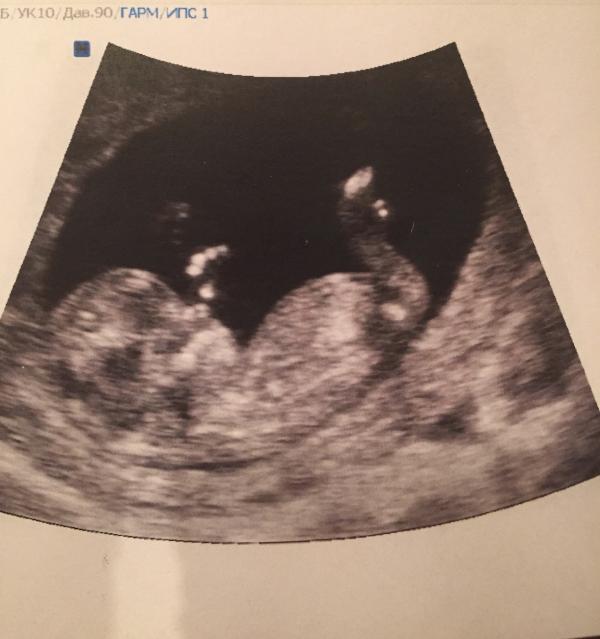

Выбегаю, плачу! Муж сразу все понимает и вызывает скорую! На улице холодно, я стою в платье, и по белым колготкам течёт кровь! Я в ужасе! Не понимаю, что происходит! Спустя 25 минут приехала скорая и меня сразу «успокаивают», мол молодая, ещё родишь.... везут в больницу, но у меня ещё есть Надежда что мой малыш там, внутри! И все будет хорошо!

Привезли в больницу, смотрят на кресле... отправляют на чистку... я в слезы! Нет, это ошибка! Так не может быть! Прошу УЗИ, и ещё раз Проверить! Меня по...